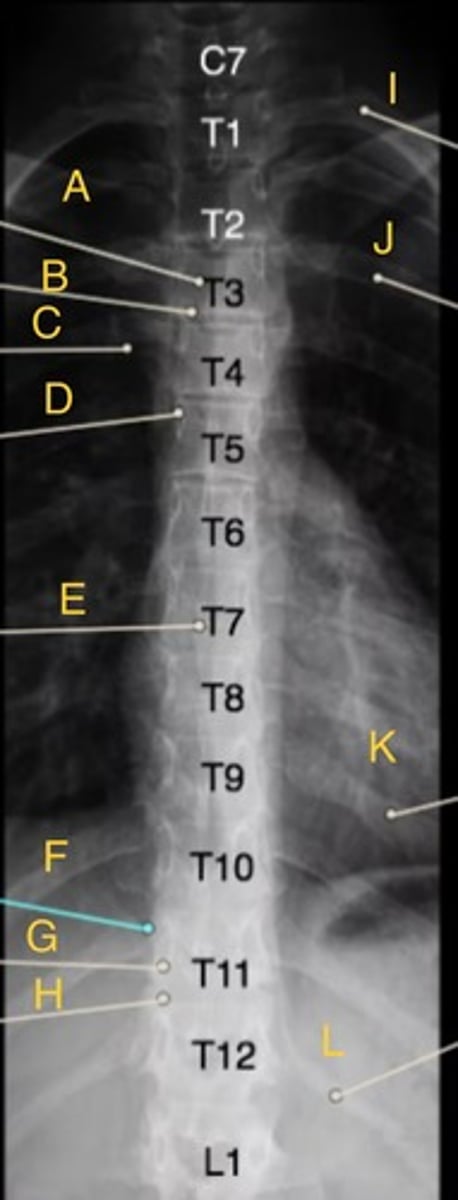

L 1st posterior rib

A.

L 10th posterior rib

B.

T11 spinous process

C.

T12 body

D.

T8-9 intervertebral disk space

E.

T7 body

F.

T1 body

G.

AP t-spine

What position?

L 1st rib

I.

L 3rd posterior rib

J.

L 9th posterior rib

K

T3 body

T12 floating rib

L